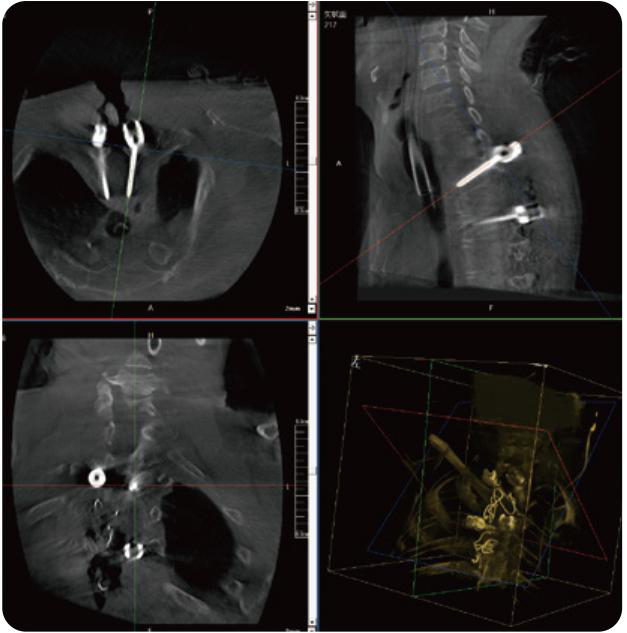

PL300B可應(yīng)用于多節(jié)段脊柱外科手術(shù),輔助醫(yī)生定位病灶部位,為脊柱外科手術(shù)(經(jīng)皮椎體成形術(shù)、椎弓根螺釘內(nèi)固定術(shù)等術(shù)式)提供術(shù)前手術(shù)流程規(guī)劃、入釘位置、角度可視化引導(dǎo),模擬仿真入釘輔助。

PL300B搭配普愛醫(yī)療自主研發(fā)生產(chǎn)的平板3D C形臂,借助一體化自適應(yīng)配準(zhǔn)( 軌跡配準(zhǔn))技術(shù),通過追蹤C形臂三維采集軌跡,自動完成圖像坐標(biāo)建立和系統(tǒng)坐標(biāo)配準(zhǔn)。配準(zhǔn)精度更高,操作步驟少,系統(tǒng)運作效率高。